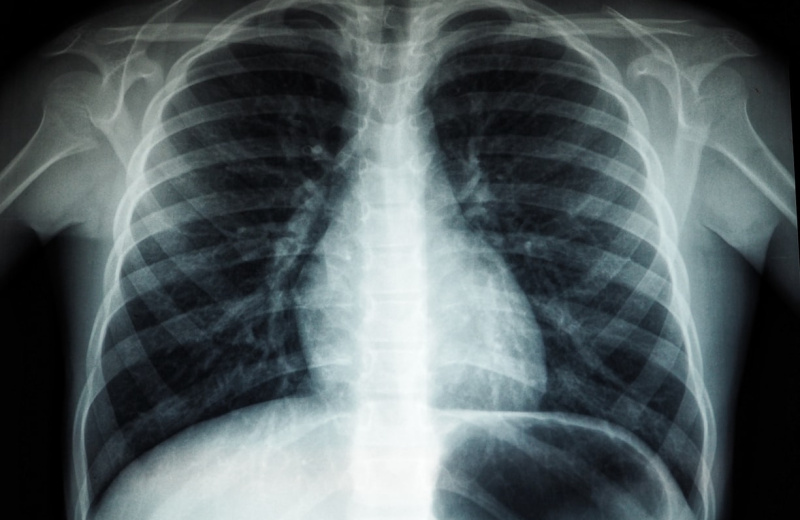

Преимущественно выявляют туберкулез легких.

Так, профилактическое обследование на туберкулёз в 2025 году прошел 80 001 житель или 86%, из них для 65 652 человек (85,2%) использовалось лучевое обследование органов грудной клетки, а для 14 223 (98,7%) применялась иммунодиагностика.